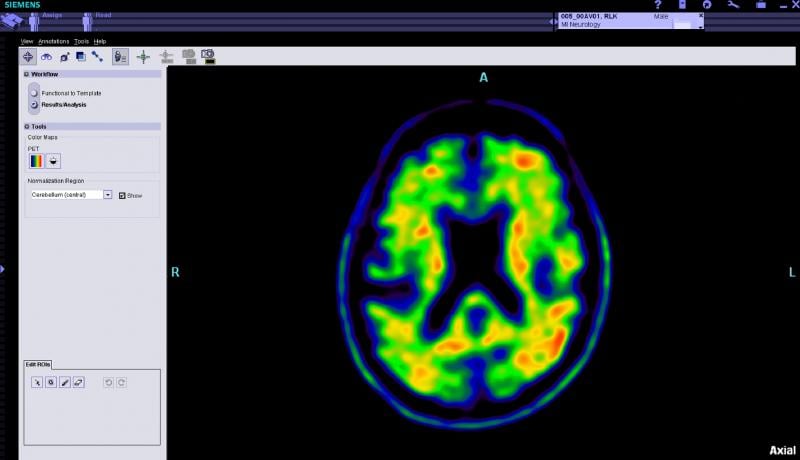

Biopharmaceuticals Inc. announced the first subject has been enrolled in its NAV4694 global, pivotal Phase 3 clinical trial. The trial will assess the safety and efficacy of NAV4694, an investigational positron emission tomography (PET) imaging agent, in detecting cerebral ?-amyloid in end-of-life subjects with and without the diagnosis of dementia. The study will examine the effectiveness of NAV4694 in detecting the presence or absence of ?-amyloid deposition in the brain by directly correlating the PET image findings during life with those of the brain tissue upon autopsy after death.

The Society of Nuclear Medicine and Molecular Imaging (SNMMI) and the Alzheimer Association have released responses to the draft Medicare decision from the Centers for Medicare and Medicaid Services (CMS) proposing Coverage with Evidence Development for the use of beta-amyloid positron emission tomography (PET) imaging agents. Both groups expressed disappointment to the CMS decision, stating that sufficient evidence exists to support immediate coverage, which would change patient management, leading to better health outcomes for patients and assisting families making care decisions.